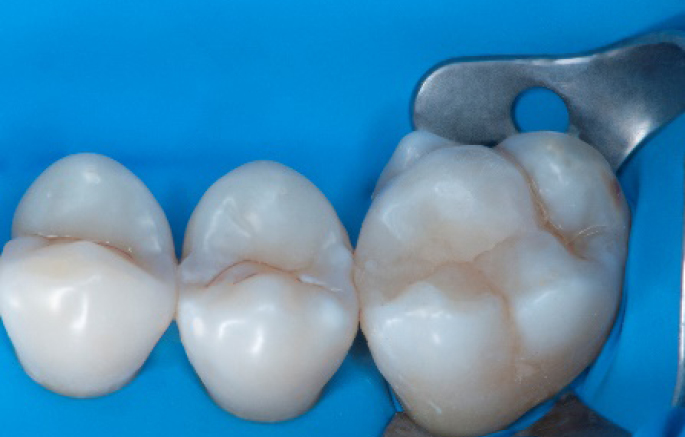

Step 9:

Transformation of a big class I into a small class I, using SDR® Plus material in one increment up to 4 mm.

Step 10:

The situation after the application of SDR® Plus material.

Step 11:

Occlusal surface restored using Spectra ST4 composite in shade A2.

Step 12:

The situation after rubber dam removal.